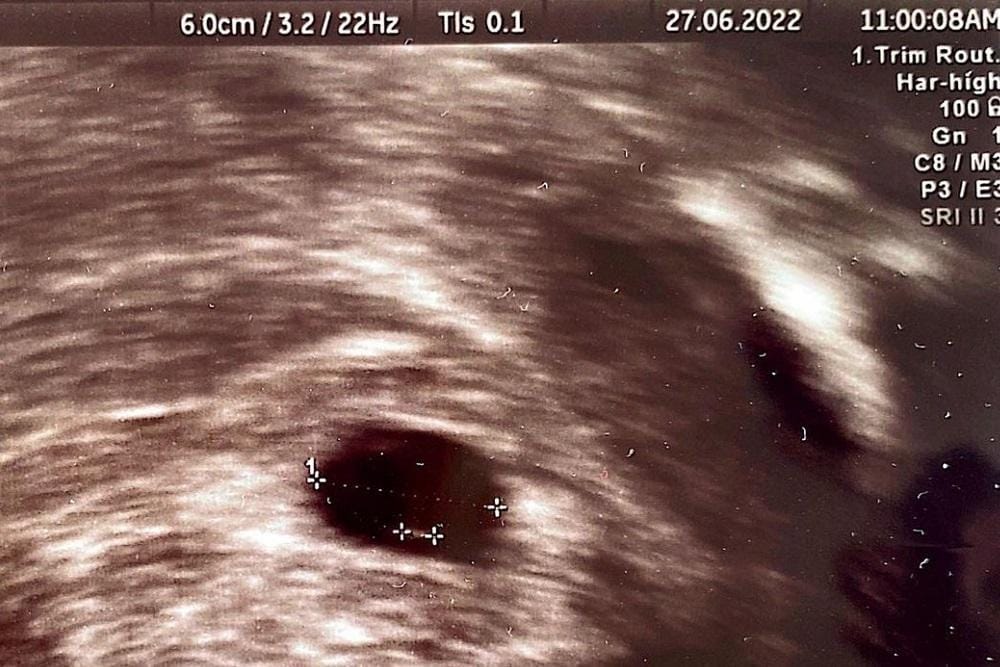

Berita bahagia itu tidak berlangsung lama. Dokter menyatakan kehamilan Annisa Pohan bermasalah. Janin yang sedang dikandungnya tidak berkembang di usia 7 minggu.

“Namun qadarullah, mungkin Allah punya rencana lain yang lebih baik. Kehamilan saya dinyatakan tidak berkembang di usia 7 minggu, ukuran baby-nya terlalu kecil dan tidak ada detak jantungnya, sehingga tidak dapat dipertahankan,” tulis Annisa.

“Saran dokter agar segera dikeluarkan dan dibersihkan dengan sistem ERPOC (serupa dengan kuret bahasa umumnya), dan telah dilakukan kemarin 2 Juli 2022,” jelasnya.